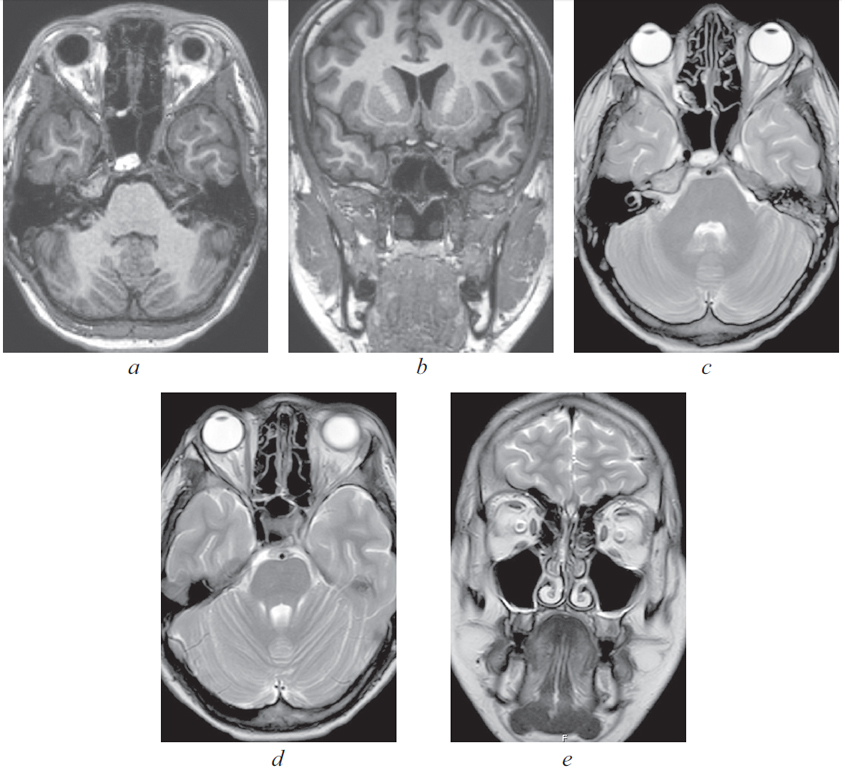

24.11.2021 выполнено МРТ головного мозга: отмечается улучшение пневматизации правых отделов пазухи клиновидной кости, левая верхнечелюстная пазуха полностью пневматизирована. Отмечается увеличение просвета сифона левой внутренней сонной артерии, отсутствие отека ретробульбарной клетчатки левого глаза, уменьшение объема тромба левого кавернозного синуса (рис. 7).

Рис. 7. Магниторезонансная томография головного мозга от 24.11.2021: а — аксиальная проекция в режиме Т1. Пневматизация пазухи клиновидной кости практически полностью восстановлена; b — коронарная проекция в режиме Т1. Сифоны внутренних сонных артерий имеют одинаковый просвет; c — аксиальная проекция в режиме Т2. Улучшение пневматизации правой основной пазухи; d — аксиальная проекция в режиме Т2. Отсутствие экзофтальма левого глаза, купирован отек ретробульбарной клетчатки слева. Увеличение просвета сифона внутренней сонной артерии слева; e — коронарная проекция в режиме Т2. Пневматизация верхнечелюстной пазухи слева полностью восстановлена

Fig. 7. Magnetic resonance imaging of the head from 24.11.2021: a – axial projection in T1 mode. Pneumatization of the sphenoid sinus is almost completely restored; b – coronal projection in T1 mode. Siphons of the internal carotid arteries have the same lumen; c – axial projection in T2 mode. Improvement of pneumatization of the right main sinus; d – axial projection in T2 mode. The absence of exophthalmos of the left eye, edema of the retrobulbar tissue on the left was stopped. Increase in the lumen of the siphon of the internal carotid artery on the left; e – coronal projection in T2 mode. Pneumatization of the maxillary sinus on the left was completely restored